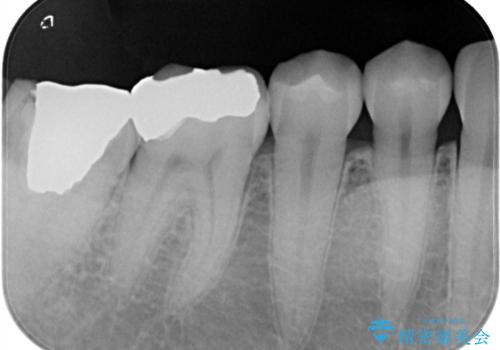

- 笑った際に目立つメタルを白くしたいとのことでご相談に来られた患者様です。下の奥歯にあるメタルインレーは、笑った際に確かに目立ちますが、それ以上にインレー自体の劣化による二次虫歯に注意しなければなりません。審美的・機能的にも優れたセラミックインレーをセットいたしました。術後の経過は良好です。

金属は真っ白に写ってしまうため、2次虫歯の有無が分かりにくいことが欠点の一つです。セラミック(ジルコニア以外)は、レントゲン写真において、実際のご自身のエナメル質と同じくらいの濃淡で写ります。そのため、定期的なメンテナンスの際に、虫歯が内部で広がっていないかのチェックをすることが可能です。